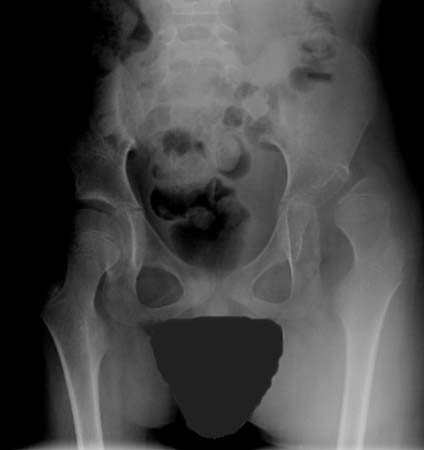

Quadril deslocado em paciente com paralisia cerebral (PC)

Do acervo de William L. Oppenheim; usada com permissão